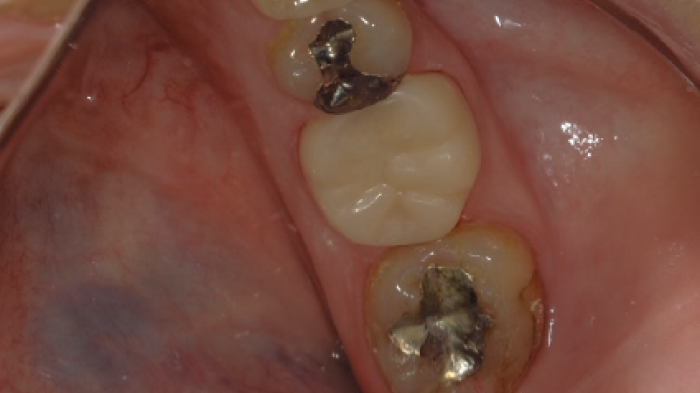

Vue de la couronne en zircone collée.